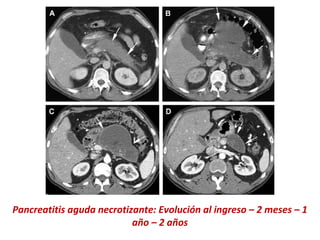

Pancreatitis aguda necrotizante: Evolución al ingreso – 2 meses – 1

año – 2 años

Pancreatitis aguda necrotizante:Evolución al ingreso – 2 meses – 1 año – 2 años